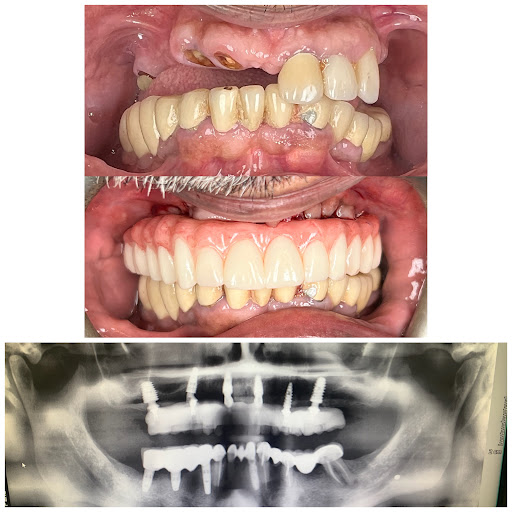

Signature Smiles Family Dentistry

Photos